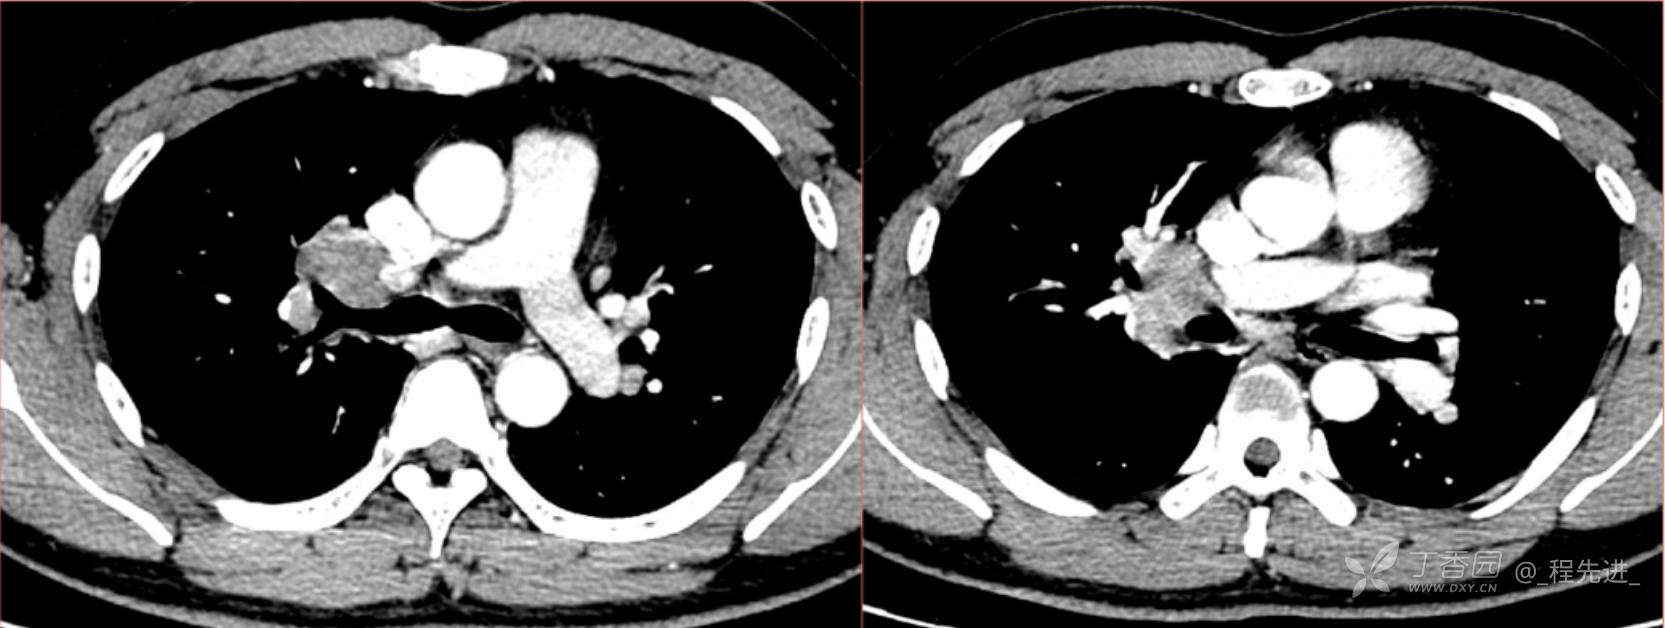

1月特别精彩病例|阵发性刺激性咳嗽,咳少量白色粘液痰1周,期待你的挑战【结果公布】

患者年龄:34岁

简要病史:患者一周前无明显诱因出现阵发性刺激性咳嗽,咳少量白色粘液痰,咳嗽无明显昼夜节律性,无发热、畏冷、寒战,无头痛、胸闷、胸痛,自行服药后 (具体不详) 症状无缓解,3天前当地医院胸片检查示右上病变

辅助检查:肺肿瘤标志物: 神经元特异性烯醇化酶(NSE): 35.72ng/ml(参考值0-16.3);非小细胞肺癌相关抗原211、癌胚抗原、糖类抗原125、铁蛋白、鳞状细胞癌抗原未见异常